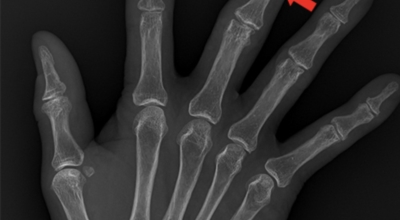

손가락 관절염 증상 - 골관절염

골관절염(및 퇴행성 관절염)은 손목, 엄지손가락 기저부에 위치한 관절, 손가락의 중간 또는 상부 관절에 영향을 미쳐요. 골관절염이 있다면 연골이 마모되어 결과적으로 뼈가 서로 마찰되어 손상돼요. 연골과 뼈의 이런 점진적 마모는 경직, 기형 또는 통증을 일으킬 수 있어요.

류머티즘 관절염은 인체의 자연 면역계가 자신의 건강한 조직을 공격하기 시작해서 관절 내막에 염증을 유발하는 자가면역 질환이지요. 이로 인해 연골이 파괴되어 결과적으로 뼈가 부식돼요. 이 만성 상태는 손목, 손, 손가락의 작은 관절에 대칭적으로 영향을 미쳐요.

그리고 손가락의 붓기가 어느 관절에 나타났느냐에 따라 의심되는 질병이 다르게 분류 되며 헤버딘 결절이라고 하여 손가락의 첫번째의 관절을 중심으로 혹 형태의 붓기와 변형의 증상이 나타나게 되며 심해질 경우, 일상생활에 지장을 초래할 수도 있겠습니다.